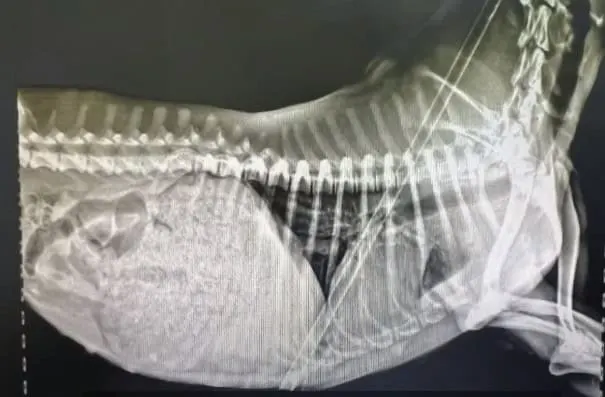

Local veterinarian Dr. Chen was called immediately. He arrived within minutes and found the dog barely breathing. The arrow had pierced her lungs and had come dangerously close to her heart. Her chest was filling with blood, and her body was growing cold. There was no time to lose.

Dr. Chen rushed her to the clinic and began emergency surgery. For two intense hours, he and his team worked to remove the arrow, stop the bleeding, and stitch the wounds that tore through both sides of her chest.